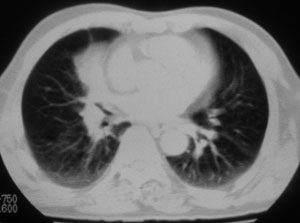

性别 男  62岁 因咳嗽及左肱骨剧烈痛疼数天来院检查。

右中央型肺癌并肱骨转移。

考虑右肺中叶肺癌并左肱骨转移伴病理性骨折。

支持右肺中心型肺癌并肺内及左肱骨转移伴病理性骨折

右肺中心型肺癌并中叶不张,左肱骨溶骨性转移并病理骨折。